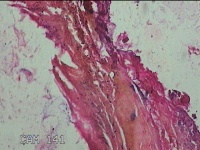

头枕部包块

性别

男

年龄

47岁

临床诊断

一般病史

发现头枕部包块10年余。

标本名称

大体所见

灰白暗红色组织4.3x2.5x1.2cm一块,表面带梭形皮肤4.3x1.7cm,皮下见包块3x1.8cm一个,切开包块呈实性,切面灰白淡黄色,质软。

图1